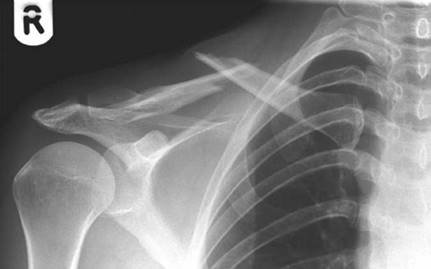

A 19-year-old rugby player presents to A&E with a first time injury to his dominant shoulder.

Comment on the radiograph.

This is an AP radiograph of the left shoulder showing an antero-inferior dislocation of the shoulder. One should look for associated injuries including greater tuberosity fractures, bony Bankart lesions and glenoid fractures.

Complications of anterior dislocation include axillary nerve palsy (5โ€“30 % ), rotator cuff tear (14โ€“63 % , increased in elderly), greater tuberosity (GT)/glenoid rim fracture ( > 20 % , = fi xation).

S tructures that may block reduction would include buttonholing through the capsule, biceps tendon, or bony fragments.

Why does the shoulder dislocate? What stops it normally?

The shoulder is a highly mobile joint, but at the expense of stability. When the restraints are overcome, the shoulder will dislocate. There are static and dynamic restraints.

Static restraints:

z O sseous anatomy limited to a third of the head on the glenoidโ€” d epth increased by labrum

(โˆผ50 % ) z Negative pressure inside joint z Capsular thickenings โ€” superior glenohumeral ligament (SGHL)/middle glenohumeral ligament (MGHL)/inferior glenohumeral ligament (IGHL) (most important โ€” hammock analogy) Dynamic restraints:

z Rotator cuff muscles z Long head (LH) of biceps tendon

The A&E staff have tried to reduce this without successโ€” talk me through how you would reduce this dislocation.

The patient has his arm externally rotated and abducted with loss of the deltoid contour. If the patient was still sedated I would attempt one further reduction in A&E. If unable to reduce I would mobilize my theatre team and anaesthetist to perform a reduction under GA:

z Hippocratic method โ€” foot in axilla on humeral head, traction on abducted arm z Kocher method of reduction โ€” flex elbow 90 ยฐ , arm in neutral, and then ER slowly until you hear a clunk of reduction. If does not reduce, flex shoulder, slowly internal rotate, and fully adduct across chest (no traction)

z Modified Stimpson โ€” hanging weight prone

If the patient was young I would splint them in an ER position for the fi rst 2 weeks then begin a mobilization programme guided by the physiotherapists.

What is the risk of this shoulder causing problems again?

The re-dislocation rate is proportional to the age at fi rst dislocation.

There is a tendency to be more aggressive in the management of young, fi rst-time dislocations. Use MRI arthrograms [look for Bankart ( ยฑ bony)/capsular tear/Hillโ€“Sachs lesion] or early EUA and arthroscopy to look for and repair Bankart lesions (labral detachment between 3 and 9 oโ€™clock).

What approach would you do for an open reduction?

Deltopectoral. (See answer to Viva 2.)